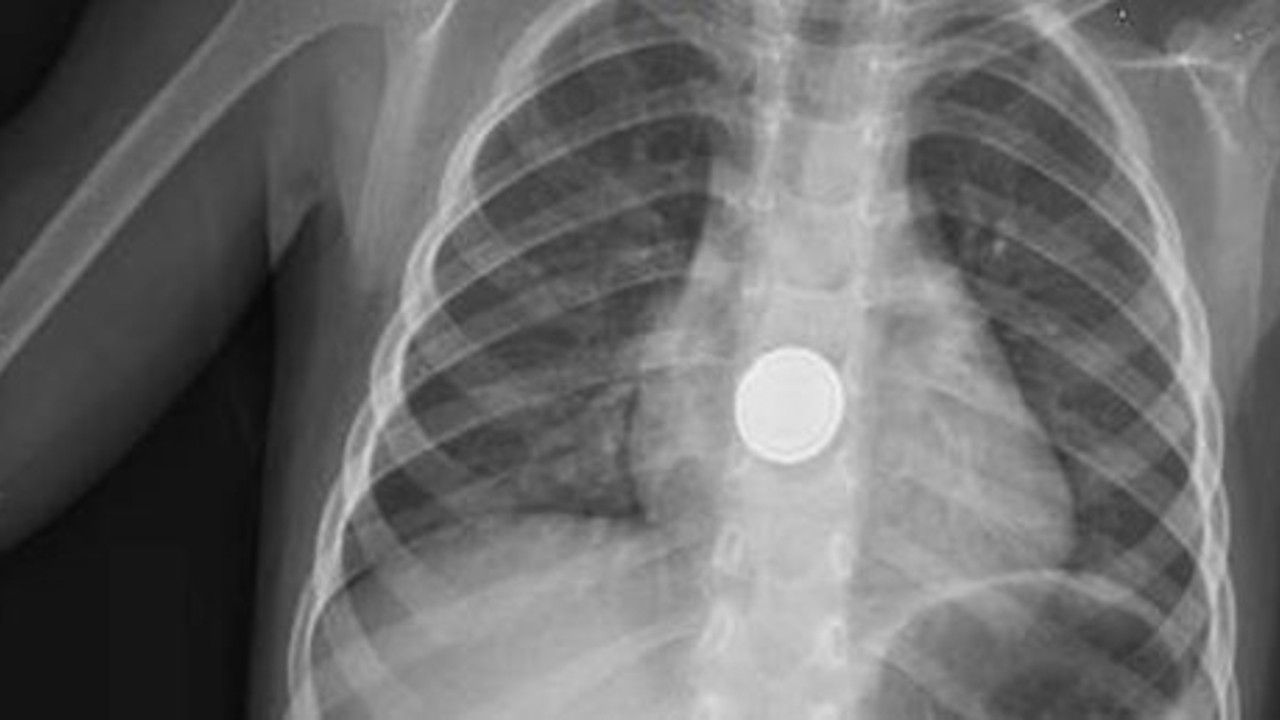

Küçük çocuğun annesine pil yuttuğunu söylemesi üzerine ailesi hastaneye başvurdu. Acil serviste ilk müdahalesi yapılan ve filmi çekilen Mehmet Efe, Çocuk Cerrahisi Uzmanı Yrd. Doç. Dr. Cemal Parlakgümüş tarafından muayene edildi. Röntgen filmindeki görüntüde pilin yemek borusunda 20 santimetre ilerleyip takıldığını belirleyen Parlakgümüş, minik çocuğu Gastroenteroloji Uzmanı Hüseyin Sancar Bozkurt'a yönlendirdi.

Bozkurt, küçük çocuğun yemek borusunu endoskopik yöntemle incelediğinde, pilin çevresindeki dokuyu yakarak hasar verdiğini gördü.

Endoskopik yöntemle yarım saatlik bir çalışmayla yerinden çıkarılan pilin, yemek borusu dokusunu yaktığı için etrafının karardığı görüldü.